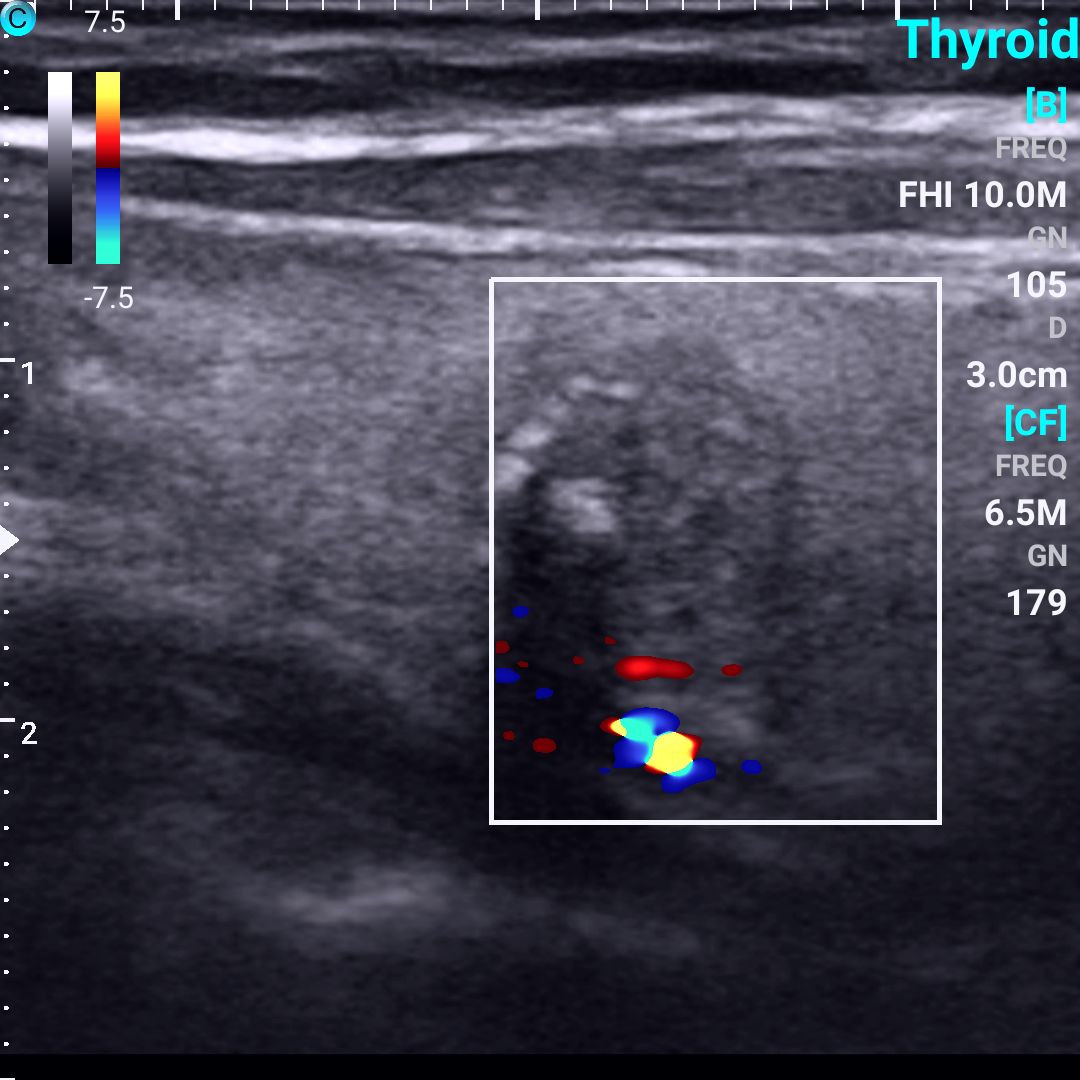

甲状腺结节中血流图像